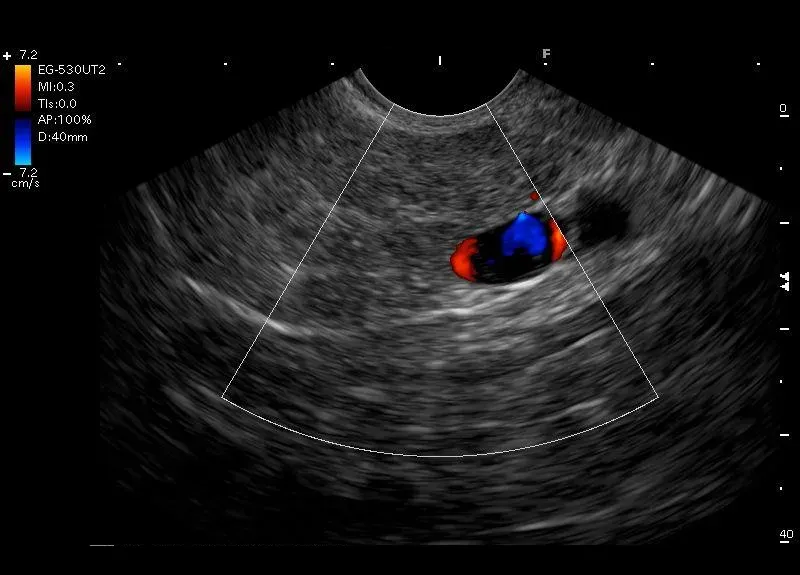

Obraz trzustki przypominający " plaster miodu" złożony z wyróżniających się stref ograniczonych hyperechogenicznymi odbiciami zwłóknień--budowa płacikowa trzustki